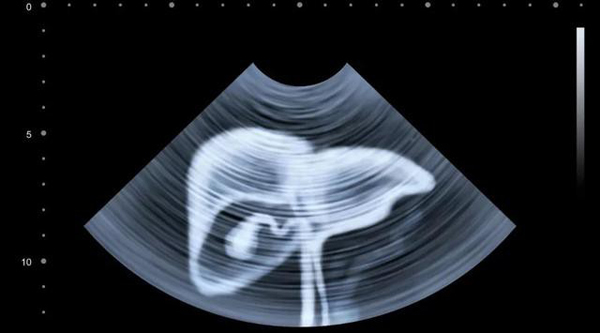

Do đó, để phát hiện ung thư gan và kịp thời chữa trị, chúng ta nên thường xuyên đến các cơ sở y tế khám và kiểm tra sức khỏe.